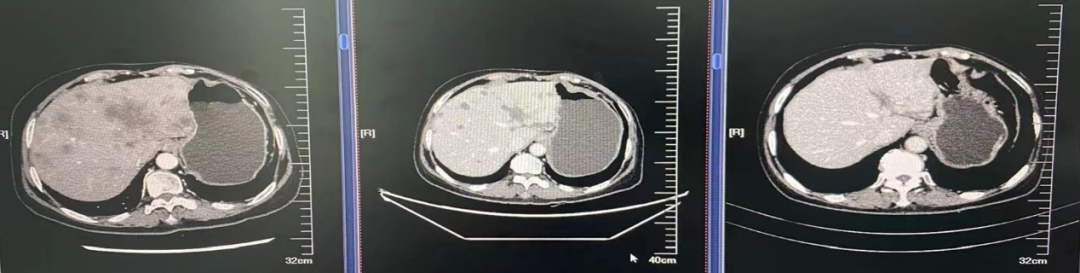

图4.肺窗

2021年4月7日双肺示:转移可能。